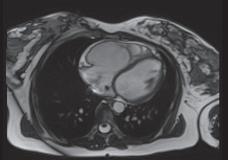

A. Ventrículo direito (VD) com volumes moderadamente aumentados e função sistólica diminuída (fração de ejeção em 3D = 33%), com hipocinesia da parede livre e da câmara de saída do ventrículo direito (CSVD), com pequenas zonas de discinesia (bulging) a nível da parede livre; B. RT a nível da parede livre do VD e CSVD, que pode corresponder a áreas de fibrose.

Figura 22.22 – Ressonância magnética. Figura amavelmente cedida pelo Dr. Nogueira da Silva (Serviço de Cardiologia do Hospital de Santa Marta, Centro Hospitalar de Lisboa Central). A B